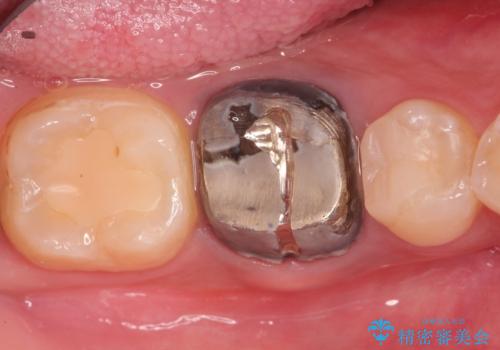

- 奥歯がズーンと痛いことを主訴に来院されました。

根管治療時に穿孔部位を認め、MTAにて修復し、分岐部の歯周ポケットおよび骨欠損に対しては、再生治療を行うことで、正常な歯周状態の獲得ができました。

歯冠修復はオールセラミッククラウンで行なっております。